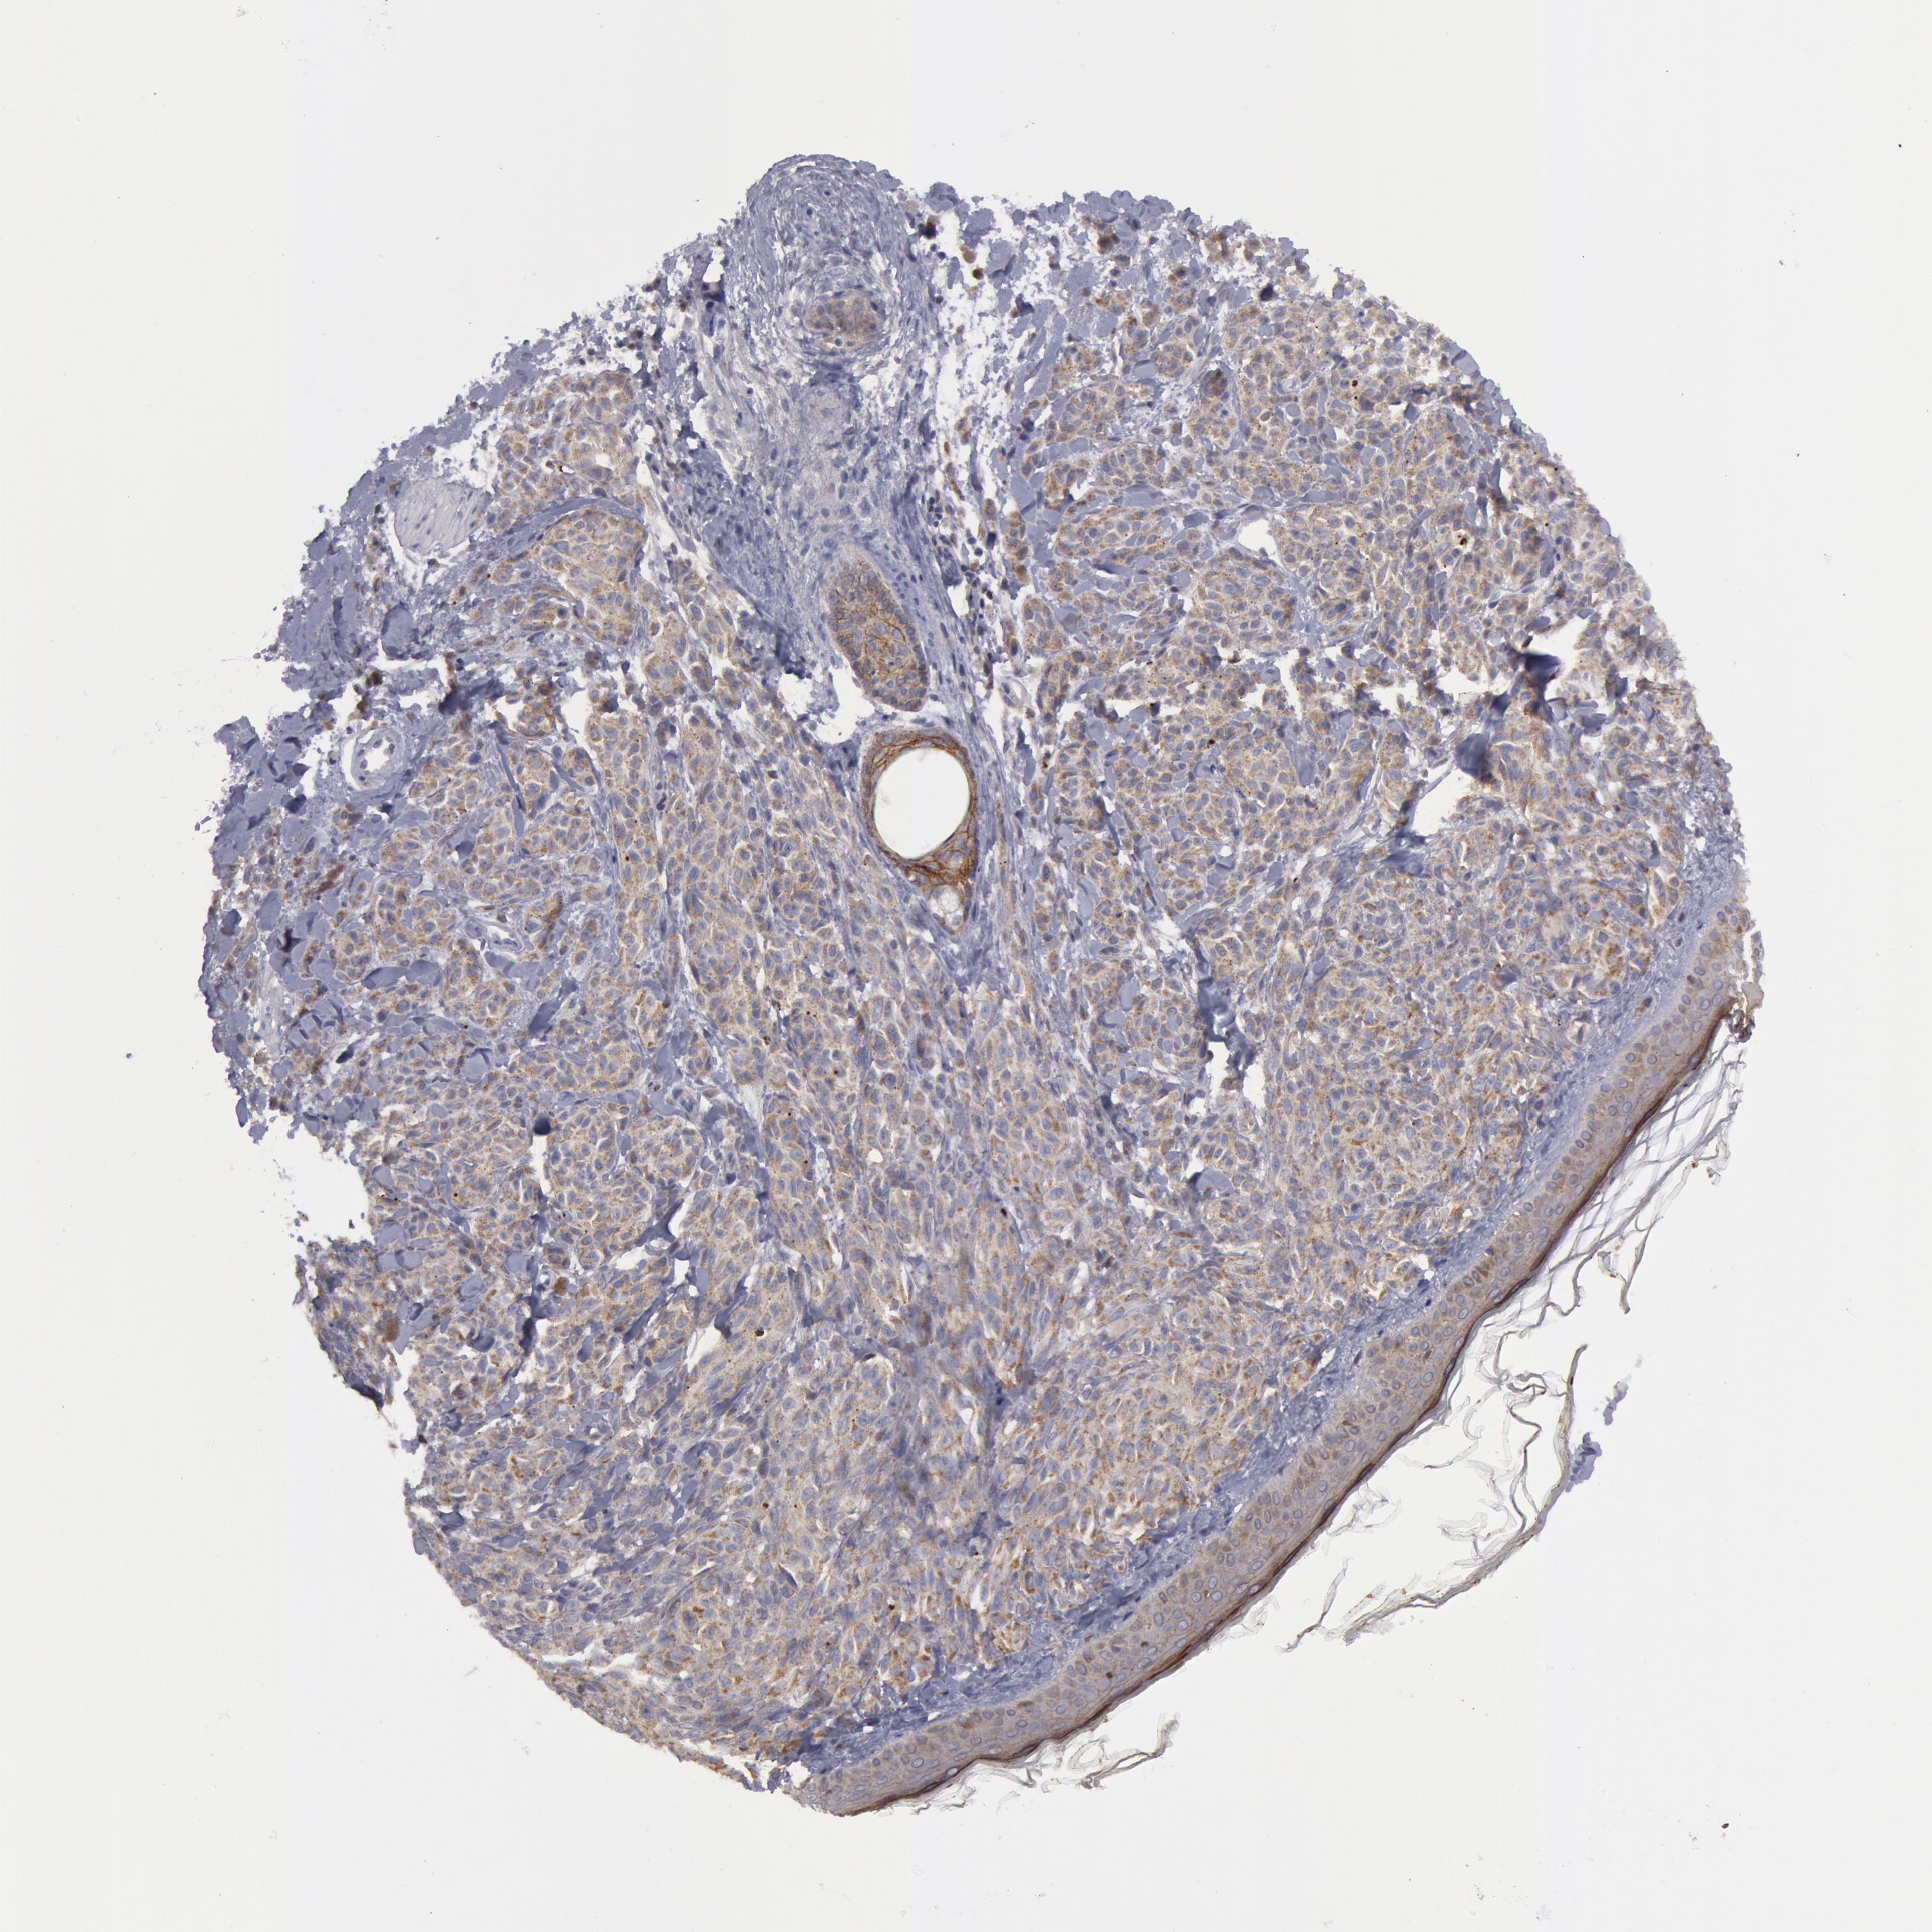

MELANOMA - Protein expressioni

A mouse-over function shows sample information and annotation data. Click on an image to view it in a full screen mode. Samples can be filtered based on level of antibody staining by selecting one or several of the following categories: high, medium, low and not detected. The assay and annotation is described here.

Note that samples used for immunohistochemistry by the Human Protein Atlas do not correspond to samples in the TCGA dataset.

Antibody stainingi

Antibody staining in the annotated cell types in the current human tissue is reported as not detected, low, medium, or high, based on conventional immunohistochemistry profiling in selected tissues. This score is based on the combination of the staining intensity and fraction of stained cells.

Each image is clickable and will lead to virtual microscopy that enables deeper exploration of all samples and also displays staining intensity scores, fraction scores and subcellular localization as well as patient and tissue information for each sample.

Antibody HPA001383

Antibody CAB000043

Antibody CAB020416

Antibody CAB062555

Staining

High

Medium

Low

Not detected

Intensity

Strong

Moderate

Weak

Negative

Quantity

>75%

75%-25%

<25%

None

Location

Nuclear

Cytoplasmic/membranous

Cytoplasmic/membranous,nuclear

Malignant melanoma, NOS

Malignant melanoma, Metastatic site